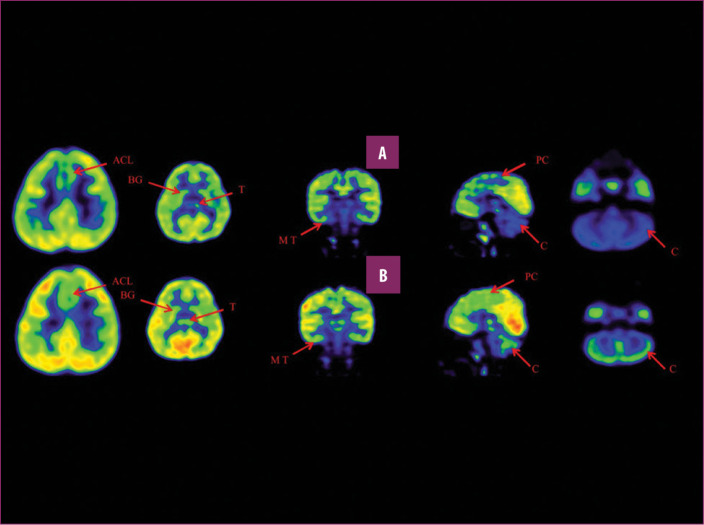

前扣帶回 (ACL)、頂葉皮層 (PC)、內(nèi)側(cè)顳葉皮層 (MT)、基底神經(jīng)節(jié) (BG)、丘腦 (T) 和小腦 (C)。B 行)第一次移植后6個月后PETCT腦部掃描的干預(yù)后圖像顯示標記區(qū)域有所改善。藍色代表代謝減退區(qū)域。綠色代表正常的新陳代謝區(qū)域。圖A和B的比較顯示藍色區(qū)域顯著減少,綠色區(qū)域增加,這表明大腦的新陳代謝得到改善。

與之前的情況相比,他在矢狀面和額狀面上的體重變化有所改善;頭部、軀干和骨盆的排列也得到改善,雙側(cè)腿筋和小腿肌肉的緊繃感也有所減輕。患者開始執(zhí)行雙手任務(wù)。在認知方面,由于他定期上學,他的注意力持續(xù)時間和久坐耐力也得到了改善。GMFM評分從60.67提高到67.75;GMFCS等級由Level3提升至Level2;和FIM評分從97分提高到99分。在比較第一次細胞治療之前和之后七個月期間進行的腦部PETCT掃描結(jié)果時,前扣帶葉、頂葉皮層、內(nèi)側(cè)顳葉皮層、丘腦、基底神經(jīng)節(jié)和小腦(表格1)。